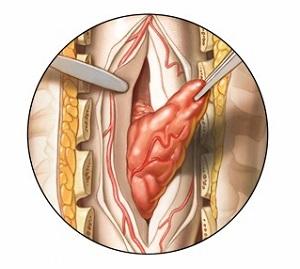

- хирургическое вмешательство (удаление опухоли высококвалифицированными хирургами);

| Хирургическое вмешательство | Удаление опухоли позвоночника. Может включать ламинэктомию, вертебропластику, кифопластику. | Метастатический рак позвоночника, первичные опухоли позвоночника (например, остеосаркома, хондросаркома), компрессия спинного мозга. Противопоказано при обширном метастазировании, плохом общем состоянии пациента. |